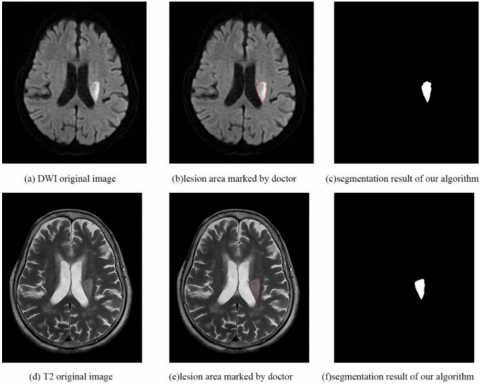

As shown in Figures 6 and 7, the segmentation results of the cascaded 3D deep residual network algorithm are similar to the delineated lesions marked by doctors, indicating that this network can quickly automatically detect and accurately segment lesions to assist doctors in quickly and accurately locating patient lesion areas for the next treatment.

As shown in Figures 6 and 7, the segmentation results of the cascaded 3D deep residual network algorithm are close to the delineated lesions marked by doctors, indicating that this network can quickly and automatically detect and segment lesions with high precision to assist doctors in quickly and accurately locating patient lesion areas for the next treatment.

Figure 6. MRI original image of Case 1, lesion area marked by doctors and segmentation result of this study

Figure 7. MRI original image of Case 2, lesion area marked by doctors and segmentation result of this study